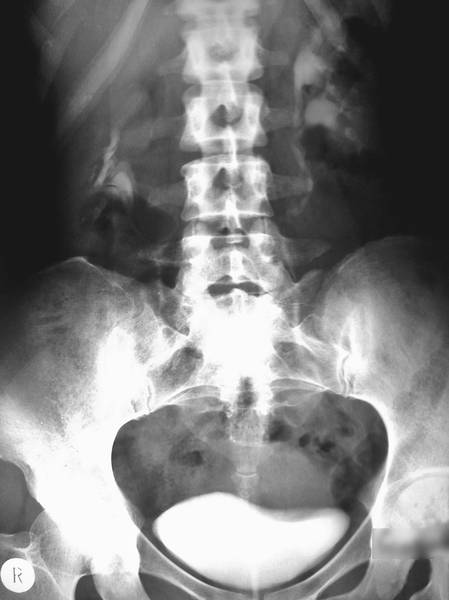

ЦИСТОГРАФИЯ

Цистография — метод исследования мочевого пузыря с помощью предварительного наполнения его жидким или газообразным контрастным веществом. Впервые её применил в 1902 г. Wittek. Цистография может быть нисходящей (экскреторной), восходящей (ретроградной) и антеградной. Нисходящую цистографию выполняют одновременно с экскреторной урографией, обычно спустя 1/2–1 ч после введения контрастного вещества.

К этому времени в мочевом пузыре накапливается достаточное количество контрастного вещества с мочой, что позволяет получить на снимке его чёткую тень (рис.).

Нисходящая цистограмма.

Нисходящую цистографию применяют в тех случаях, когда по каким-либо причинам невозможно ввести катетер в мочевой пузырь и, следовательно, выполнить восходящую (ретроградную) цистографию.

Противопоказания к ретроградной цистографии: острые воспалительные процессы в мочеиспускательном канале, мочевом пузыре, простате, семенных пузырьках и органах мошонки.

При цистографии мочевой пузырь должен быть наполнен контрастным веществом в достаточной степени, в противном случае тень пузыря на цистограмме окажется деформированной, что может повлечь за собой диагностическую ошибку. Нормальный, хорошо наполненный мочевой пузырь на цистограмме имеет гладкие ровные контуры. Его форма пузыря может быть круглой, овальной, продолговатой или пирамидальной. У мужчин чаще всего тень мочевого пузыря округлая, у женщин — овальная, причём поперечный диаметр больше продольного и присутствует некоторая вогнутость верхнего контура. Нижний край тени мочевого пузыря расположен на уровне верхней границы симфиза или выше её на 1,0–1,5 см, а верхний — достигает уровня III–IV крестцового позвонка. Верхний контур мочевого пузыря имеет несколько большие размеры, чем нижний. В норме на цистограмме мочеиспускательный канал и мочеточники не заполнены контрастным веществом.